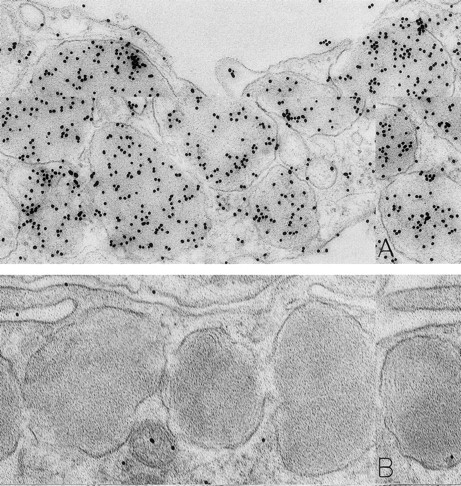

Mast cells in skin biopsies obtained 1 hour 40 minutes (A) or 2 hours (B) after the SC injection of 25 or 5 μg/kg rhSCF, respectively, in patients no. 3 (A) and no. 1 (B), who had received daily SC injections of rhSCF for 13 days. Reactivity for histamine is indicated by DAO-gold labeling in the cytoplasmic granules of a mast cell that exhibits no morphologic evidence of secretory activity (A); DAO-gold label is absent when the grid containing a section of the specimen was digested with DAO before staining with DAO-gold (B). Original magnifications: (A) ×67,500; and (B) ×75,000.

Specificity controls for the histaminase-gold-based affinity technique, including absorption of the DAO-gold reagent by solid-phase histamine before sample staining (Figs 2C and 3C) and digestion of the section with histaminase before DAO-gold staining (Figs 1B and 3D), showed a marked reduction of label or a complete absence of reactivity. In every case tested, there was no staining of sections with colloidal gold alone (data not shown).